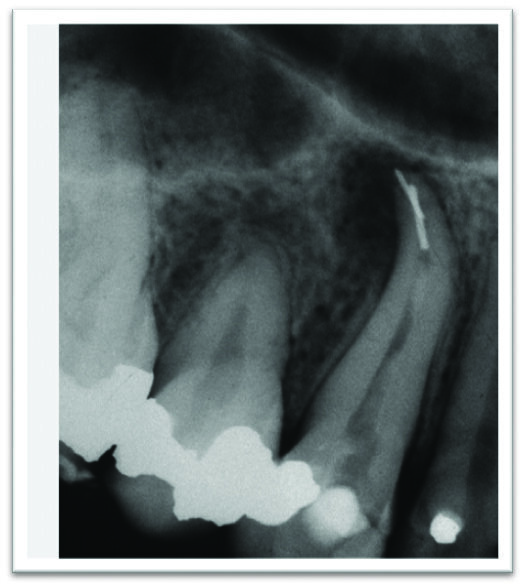

The prognostic impact of a retained separated instrument on endodontic treatment and retreatment has been investigated in only a few studies, most of which are based on small numbers of cases. Recent clinical studies document that prognosis is not significantly affected by the separated instrument itself. Prognosis depends on how much undebrided and unobturated canal apical to and including the instrument remains. The outcome is better if the canal was instrumented to the later stages of preparation when the separation occurs4. If vital and uninfected pulp tissue was present, and there was no apical periodontitis, the presence of the separated instrument should not affect the prognosis5. If the instrument can be removed without causing iatrogenic complications such as perforations, ledging, extrusion of the fragment through the apex, or excessive weakening of tooth structure (Figure 1), the prognosis will not be affected. However, if the instrument cannot be removed or bypassed in a tooth with a necrotic infected pulp and apical periodontitis, the prognosis will be uncertain. These cases should be followed closely and if symptoms persist, apical surgery or extraction should be considered4.

Figure 1. Separation of a second instrument while attempting to remove the first separated instrument is not uncommon.